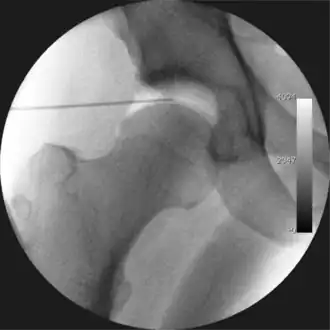

Intraoperative fluoroscopic image during an arthroscopic resection of a cam lesion of the femur. The upper instrument is the arthroscope (viewing device), while the lower is the high-speed burr used for reshaping the bone.

The next step is to insert a fine needle under x-ray guidance into the hip joint. This breaks the 'suction seal' of the joint and allows further distraction if necessary (see fig 4). The surgeon wishes to see the ball move out the socket by approximately 1 cm, so that access to the hip joint can be achieved with minimal risk of damage to the joint surfaces. Most surgeons will inject fluid into the joint at this stage, again to ensure that there is enough space between the ball and socket for safe instrument access. This needle is then removed. The next step is placement of the 'portals', or the small holes made to pass instruments into the joint. This is achieved by again passing a fresh hollow needle into the joint under x-ray control, usually in a slightly different position. The reason for this is so the surgeon can ensure that the needle, and subsequent cannulae do not penetrate and damage the acetabular labrum or cartilage joint surfaces (see fig. 5). Again, surgeons will have their own preferences as to their preferred placement. Through this hollow needle, a long thin flexible guide wire is passed into the joint, and the needle is removed over it, leaving the guide wire in situ. A small cut in the skin is made around the wire, to allow for larger cannulae to be placed over the wire through the portal. The wire therefore guides the larger cannulae into the joint. The most common external diameters of cannulae used are between 4.5 and 5.5 mm. Once the surgeon is satisfied that the cannula is in the correct position, by a combination of feel and x-ray guidance, the guide wire can be withdrawn. Once the first portal is correctly placed, any further portals may be created once the camera is in position, to ensure that they are placed with minimal risk to the joint surfaces. This process can be repeated to gain as many points of entry to the hip joint as the surgeon requires, normally between two and four. Certain of these entry points will be used for the viewing arthroscope and others for operating instruments.

Standard arthroscopic treatment of symptomatic cam FAI involves debridement (resection) or repair of any labral [10] and chondral injuries [11] in the central compartment of the hip, and subsequent reshaping of the head-neck junction of the upper femur (osteochondroplasty) in the peripheral compartment [12][13] using high-speed motorised burrs that are similar in design to a dentist's drill (see fig. 9).